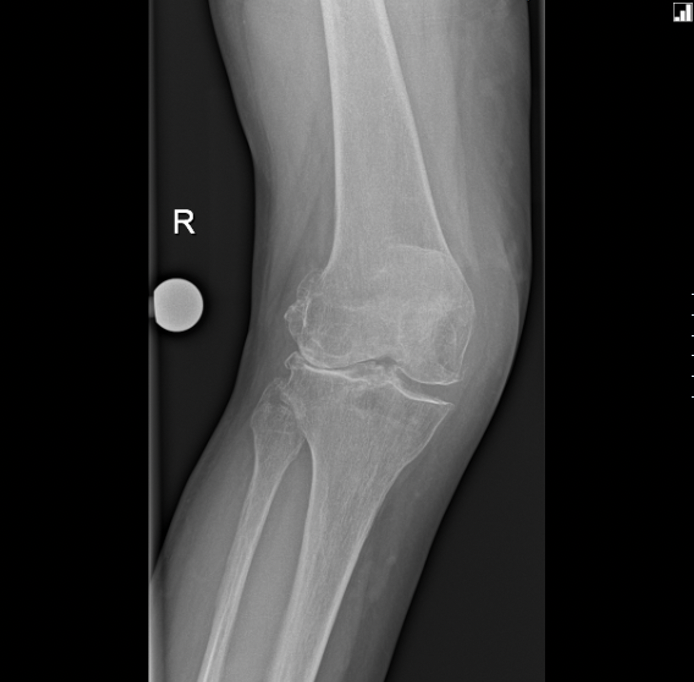

Knee joint implant replacement xray showing in medical orthpodedic New Alternative To Total Knee Replacement here, hss surgeons edwin p. this technology could be an alternative to current treatment methods, such as autografting or total knee replacement. learn about various treatments that may help manage knee pain without surgery, such as weight loss, exercise, injections, acupuncture,. journey deuce is a new technology that allows surgeons to replace only the damaged part. New Alternative To Total Knee Replacement.